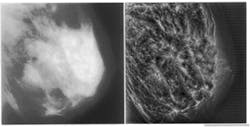

Detection of early malignancies while they are still small is problematical, especially in younger women who have denser breast tissue, because of the minor difference in x-ray attenuation between normal glandular tissues and malignant disease (see Fig. 1, left). Although calcifications present with malignancy may have high inherent attenuation properties, their small size also results in a low subject contrast. As a result, tumor detection will always be difficult in mammography done with analog film or screen imaging. Because mammograms display only about 3% of the information they detect, improvements in detection of small tumors and microcalcifications are more likely to occur by improving the visibility of these features.

FIGURE 1. Lack of contrast makes dense-tissue mammograms particularly difficult to diagnose (left); image gains in contrast after global wavelet processing for four levels of analysis (right).